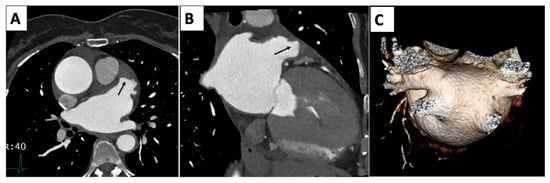

| Imaging Modality | Imaging Illustrations | Description |

|---|---|---|

| Echocardiography | ![]() | Mild left-ventricular dilation and systolic dysfunction |

| Cardiac MRI | ![]() | Short-axis view reveal interventricular mid-myocardial LGE (black arrow). |

| Cardiac CT | ![]() | Left-anterior descending artery on cardiac CT |

| Nuclear | ![]() | Normal fluorodeoxyglucose uptake in the myocardium |